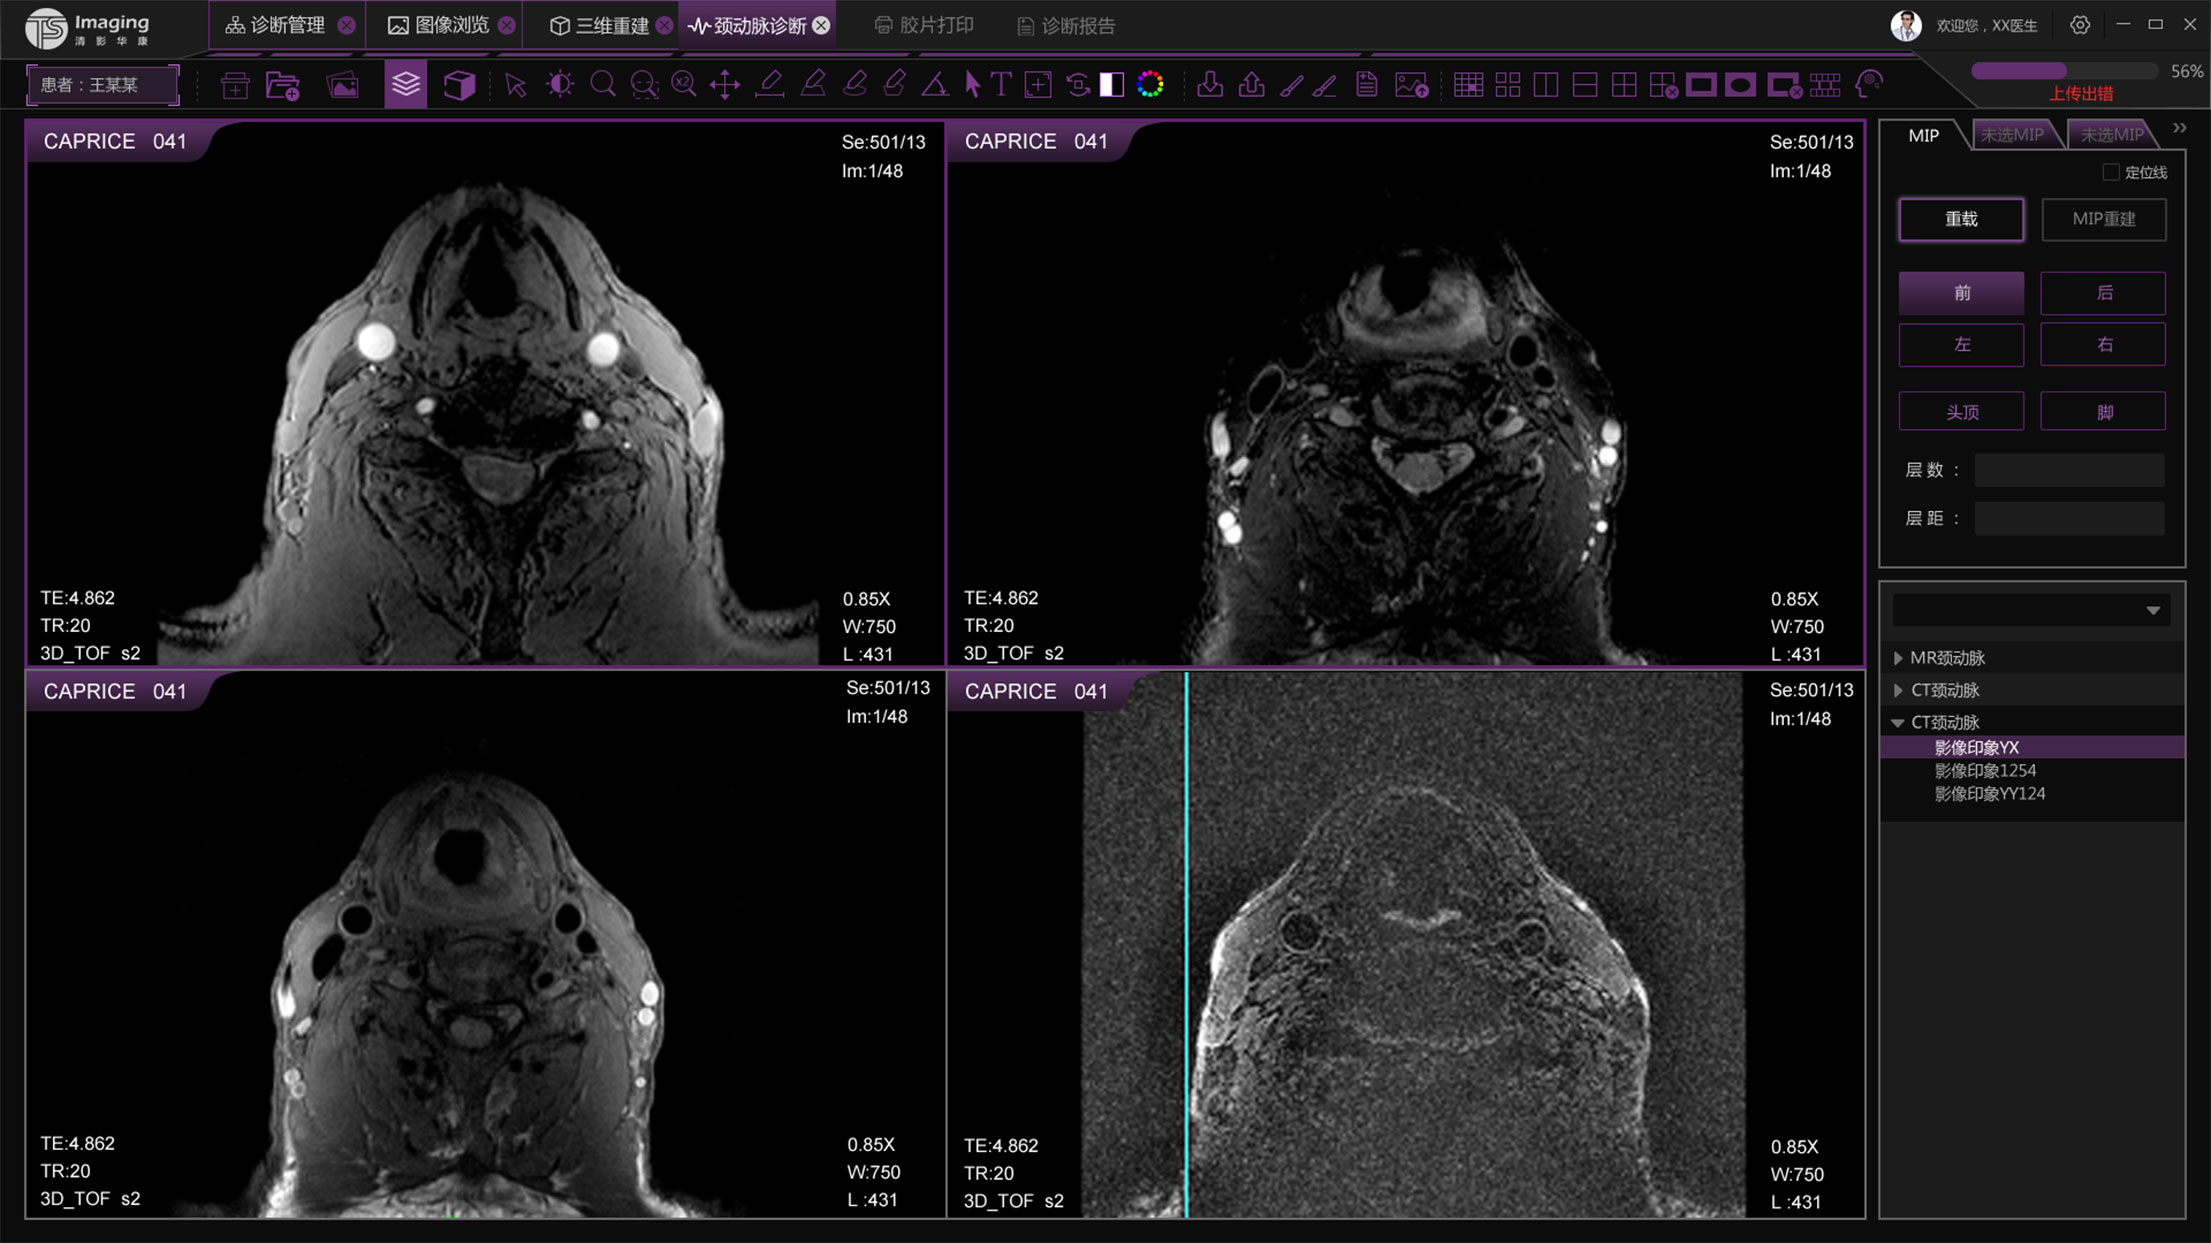

三維重建頁面

三維重建頁面從用戶的使用習慣上把操作按鈕放到了右側,進行交互上的優化,上側的操作按鈕進行統一設計和現有頁面保持風格的統一。左側的操作區域可收縮,收起來時可更好的展示圖像。